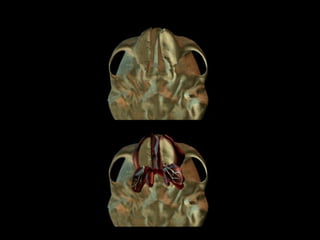

Palate - Development

• Palatal shelves

rotate to the

horizontal position

• Fuse from anterior

to posterior to

form the palate by

12 weeks

• 9.

Palate - Development •Palatal shelves rotate to the horizontal position • Fuse from anterior to posterior to form the palate by 12 weeks